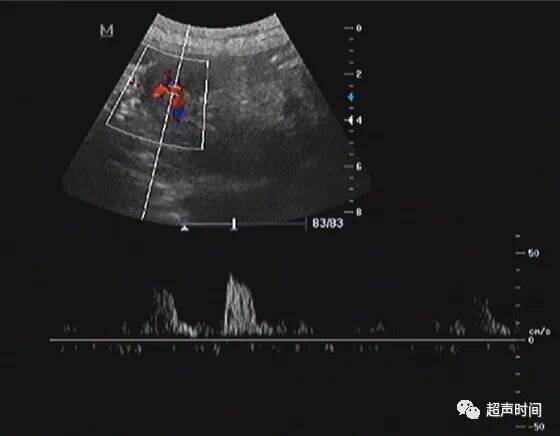

胃窦壁不规则增厚,回声减低, CDFI :其内可见高阻血流。胃窦壁僵直,探头按压长时间不蠕动。余胃壁蠕动良好。

图 6 CDFI : 增厚的胃窦壁内可见粗大的高阻血流